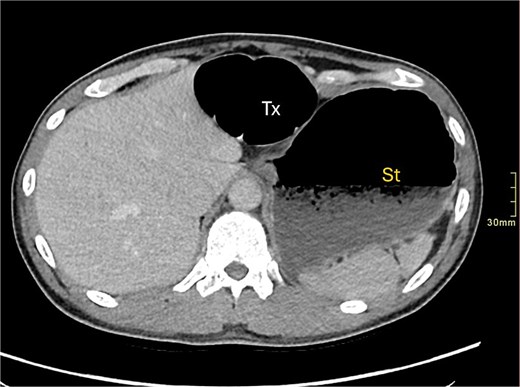

A contrast-enhanced computed tomography (CT) scan of the abdomen and pelvis demonstrated a large bowel obstruction with a transition point at the distal transverse colon with swirling of the mesentery. Downstream large bowel was collapsed. Upstream dilatation included the terminal ileum suggested an incompetent ileo-caecal valve. The gastric antrum was also involved in the internal hernia, resulting in gastric outlet obstruction. See Figs 1–5.

Axial CT image displaying transverse colon in paraduodenal hernia (PDH) with resulting distension of transverse colon (Tx) and stomach (st).